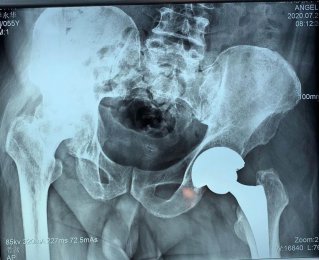

專于骨科,精于微創(chuàng)。濰坊市市立醫(yī)院骨二科以骨科微創(chuàng)為主要特色,致力于用最小的創(chuàng)傷治療疾患,并結(jié)合ERAS理念,創(chuàng)建無痛手術(shù)、無痛病房,給予患者最快最佳的術(shù)后恢復(fù)??剖议_展髖膝關(guān)節(jié)疾病的個(gè)體化治療,充 分評(píng)估患者髖膝關(guān)節(jié)功能,從采用不同的 手術(shù)方案治療髖膝關(guān)節(jié)疼痛; 開展 微創(chuàng)經(jīng)皮椎弓根螺釘內(nèi)固定術(shù)、經(jīng)皮椎體成形術(shù)(PVP、PKP)術(shù)、MIPPO技術(shù)等各種骨科...[全文閱讀]

近日,濰坊市市立醫(yī)院骨二科為50歲的徐先生行右膝關(guān)節(jié)骨關(guān)節(jié)炎單髁關(guān)節(jié)置換術(shù)?;颊咝g(shù)后恢…【查看詳細(xì)】

專于骨科,精于微創(chuàng)——骨二科近日完成一例膝關(guān)節(jié)骨性關(guān)節(jié)炎單髁關(guān)節(jié)置換手術(shù)